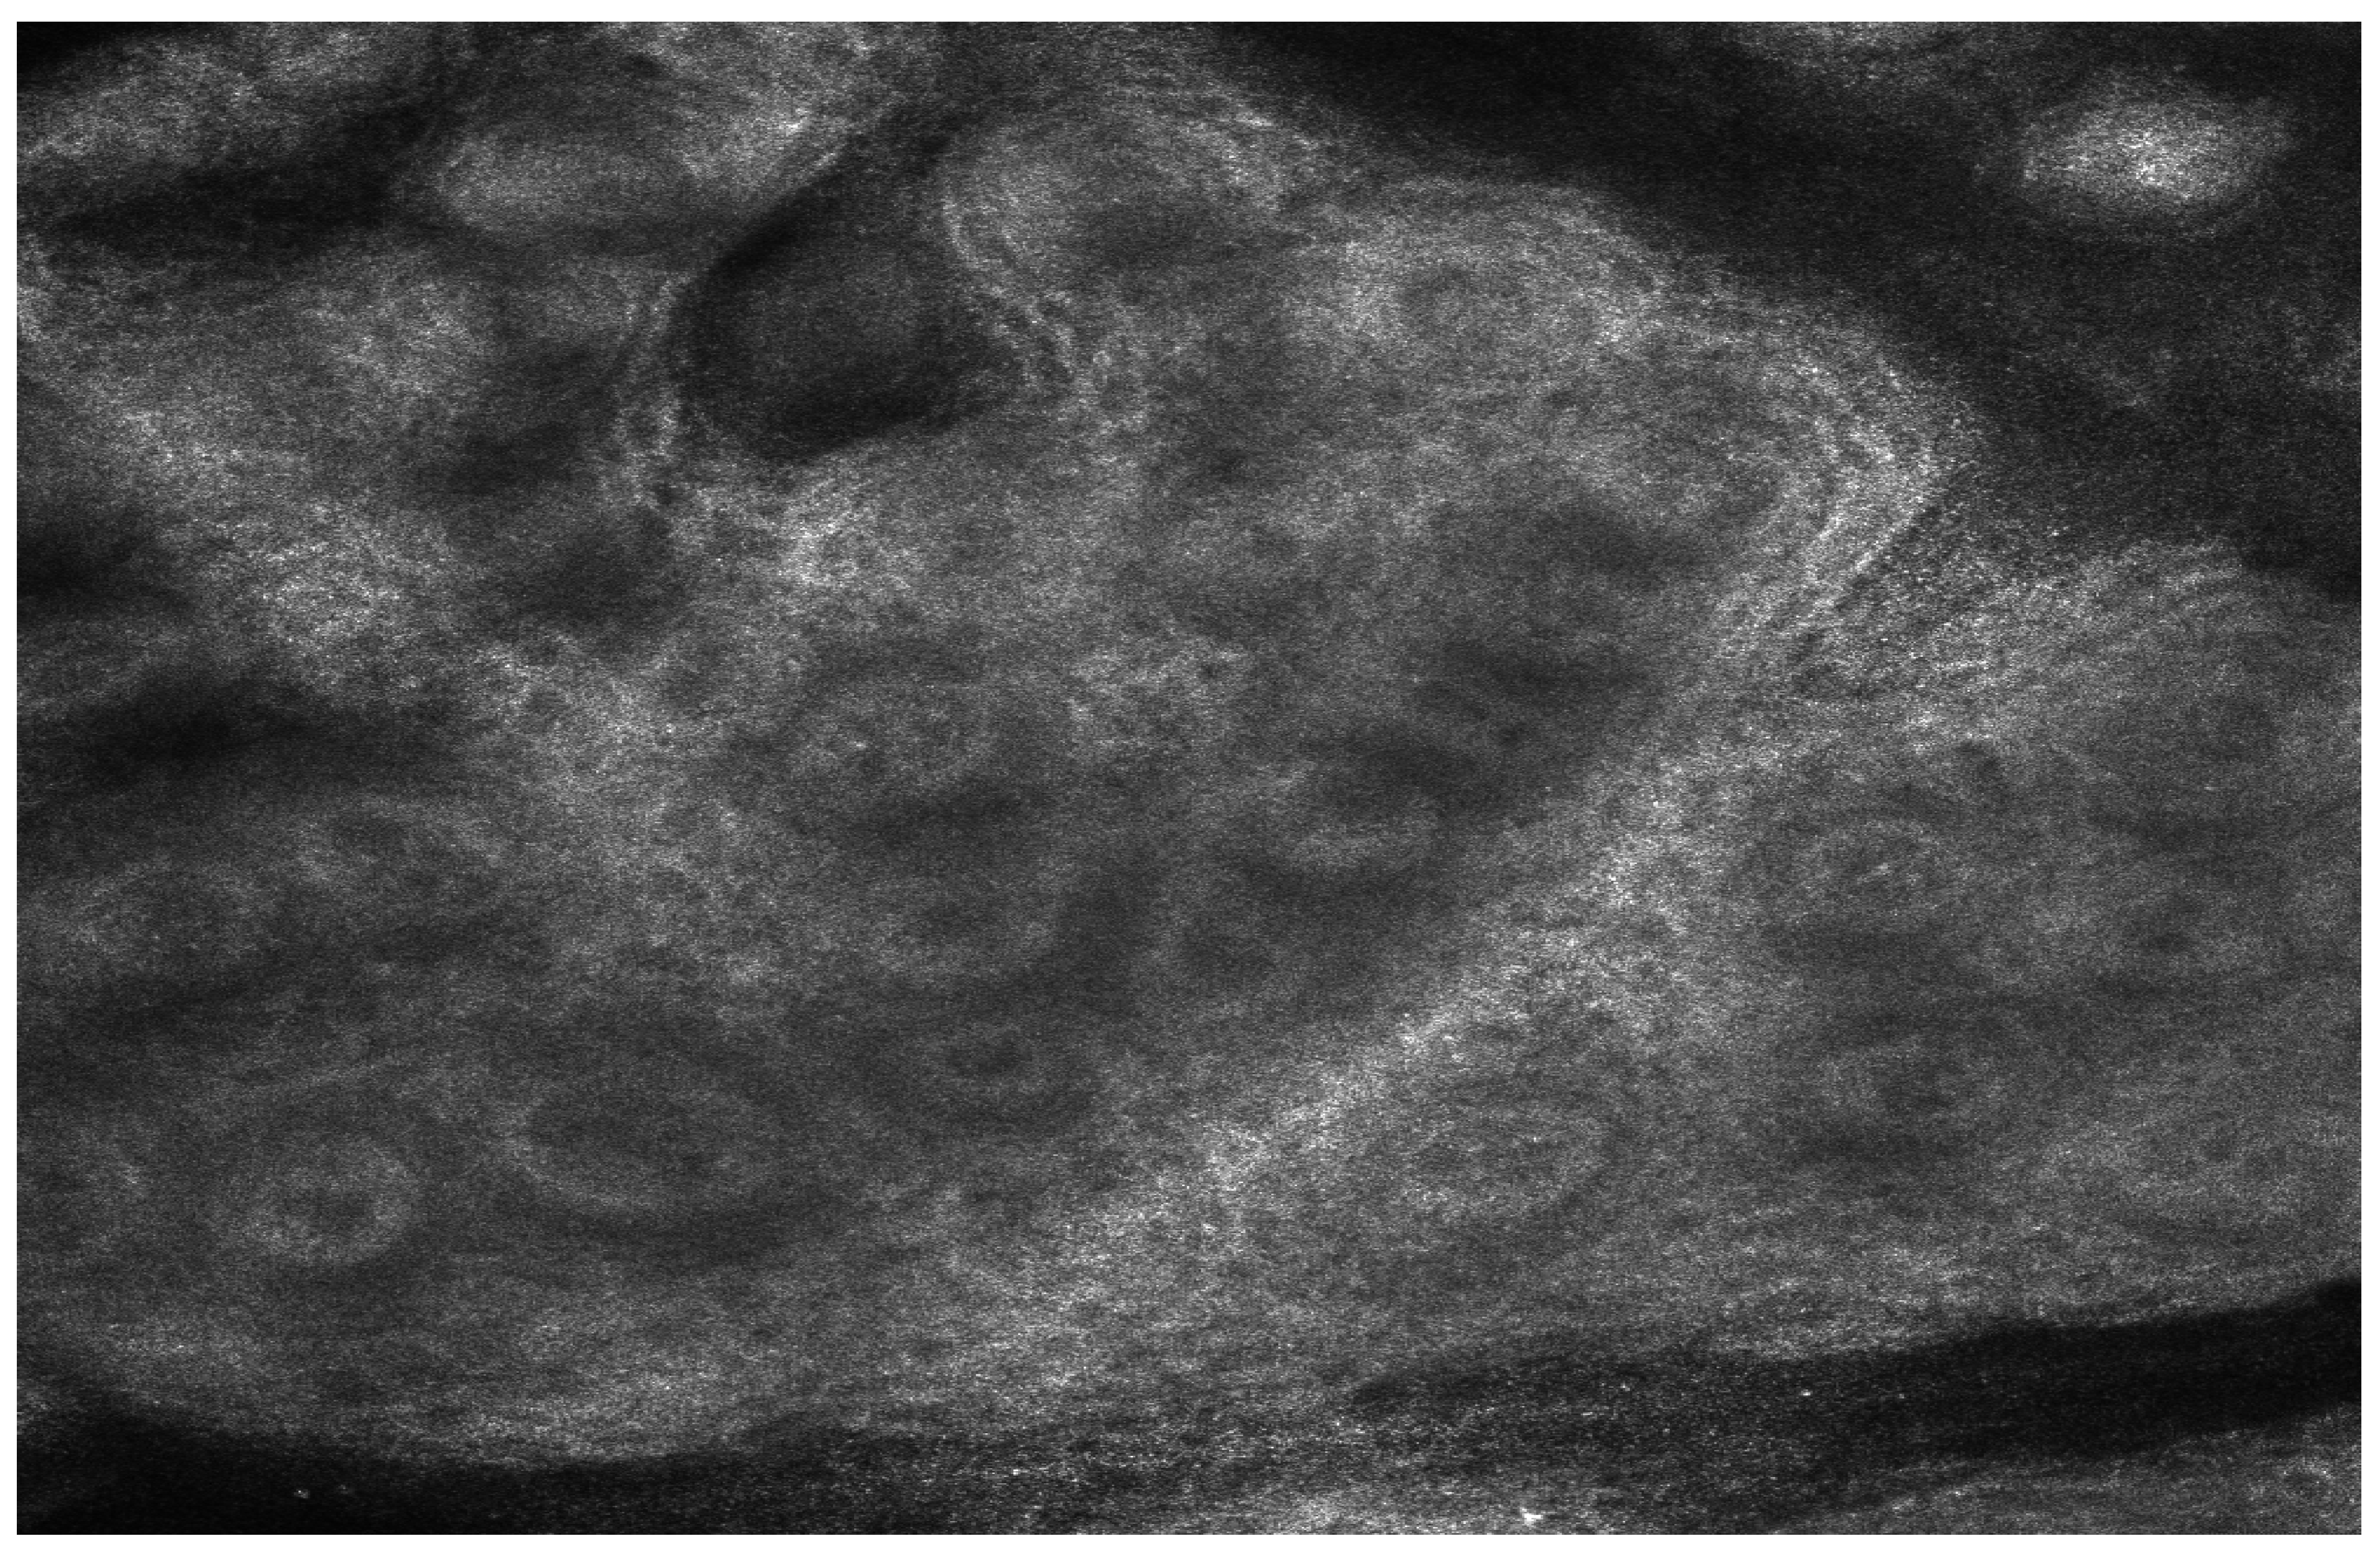

In vivo confocal microscopy allowed us to observe structural changes in the epidermis and alterations in melanocyte activity following biologic therapy. These findings suggest a potential link between cytokine modulation and epidermal remodeling. Before starting treatment, the “edged papillae” appearance (bright papillary structures) was absent, likely due to high epidermal turnover and elevated levels of inflammatory cytokines, particularly TNF-α, IL-17, and IL-23 (Figure 1 and Figure 2).

Figure 1. Reflective confocal microscopy aspect before the initiation of biologic therapy—absence of edged papillae visualization, accompanied by pronounced epidermal thickening and inflammatory infiltration.

Figure 2. Reflective confocal microscopy aspect before the initiation of biologic therapy—alternative aspect—absence of edged papillae visualization, accompanied by pronounced epidermal thickening and inflammatory infiltration.